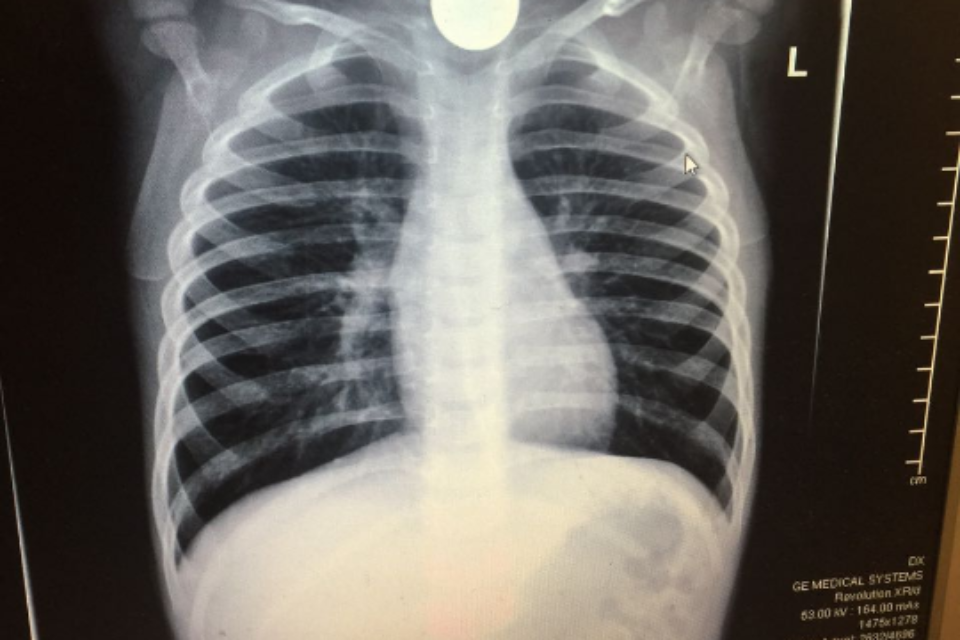

מטבע 10 אג' בוושט הפעוט // צילום: דוברות הדסה // מטבע 10 אג' בוושט הפעוט // צילום: דוברות הדסה

סדרת בדיקות ובכללן בדיקת רנטגן הבהירו ללא כל צל של ספק כי חפץ עגול ושטוח היה נעוץ בוושט של הפעוט. ד"ר מרדכי סליי, רופא גסטרו ילדים בכיר הוזעק בדחיפות למיון ילדים והחל בפעולות חילוץ מידיות של החפץ אשר עלול היה לגרום לסיבוכים ניכרים עד כדי התערבות ניתוחית ואף לסיכון חייו של הילד.

"היה ברור כי הילד במצוקה" אמר ד"ר סליי והוסיף כי "על מנת לבצע את הפרוצדורה, היה צורך להרדימו. החפץ גלש לקיבה ומשם שלפנו אותו בזהירות רבה. אז התברר כי הפעוט בלע מטבע של עשר אגורות, כאשר אף אחד לא שם לב".